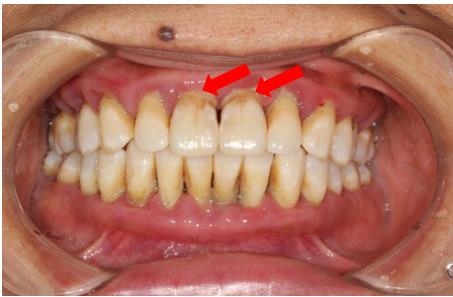

臨床表現(xiàn)變化: